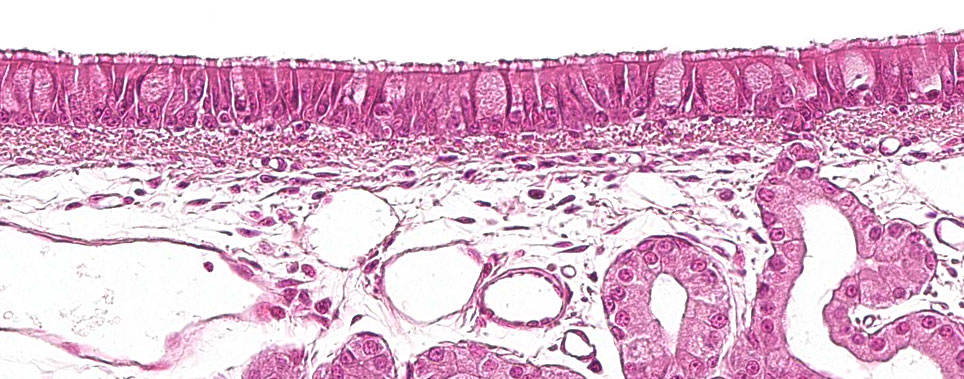

A primeira parte do sistema respiratório, a porção condutora ou vias aéreas, vai da cavidade nasal até às últimas ramificações dos bronquíolos, e também inclui os seios nasais e paranasais que estão conectados à cavidade nasal, nasofaringe e laringe. Todas estas estruturas tubulares estão revestidas por um epitélio pseudo-estratificado ciliado com células caliciformes (figura 1), responsável por um dos principais sistemas de defesa da mucosa respiratória, o aparelho mucociliar. Este sistema é composto pelos cílios das células do epitélio respiratório, junto com as secreções das células caliciformes e as glândulas seromucosas que aparecem sob a mucosa respiratória e a sua principal função é eliminar as partículas que entram através do ar inspirado. As glândulas segregam um líquido claro, de baixa viscosidade e rico em proteínas, que se dispõe entre os cílios, formando um meio que favorece seu movimento para cima. O muco segregado pelas células caliciformes é depositado nos cílios e permite a aderência das partículas inaladas. O movimento ascendente dos cílios empurra o muco em direção à parte superior do sistema respiratório, que pode ser engolido e passado para o sistema digestivo, onde é digerido, ou expelido para fora pela boca e/ou cavidade nasal. Agentes como Mycoplasma hyopneumoniae, que provoca a perda dos cílios, ou vírus como Influenza suína ou o coronavírus respiratório, que provocam a destruição das células epiteliais, destruindo este sistema de defesa.